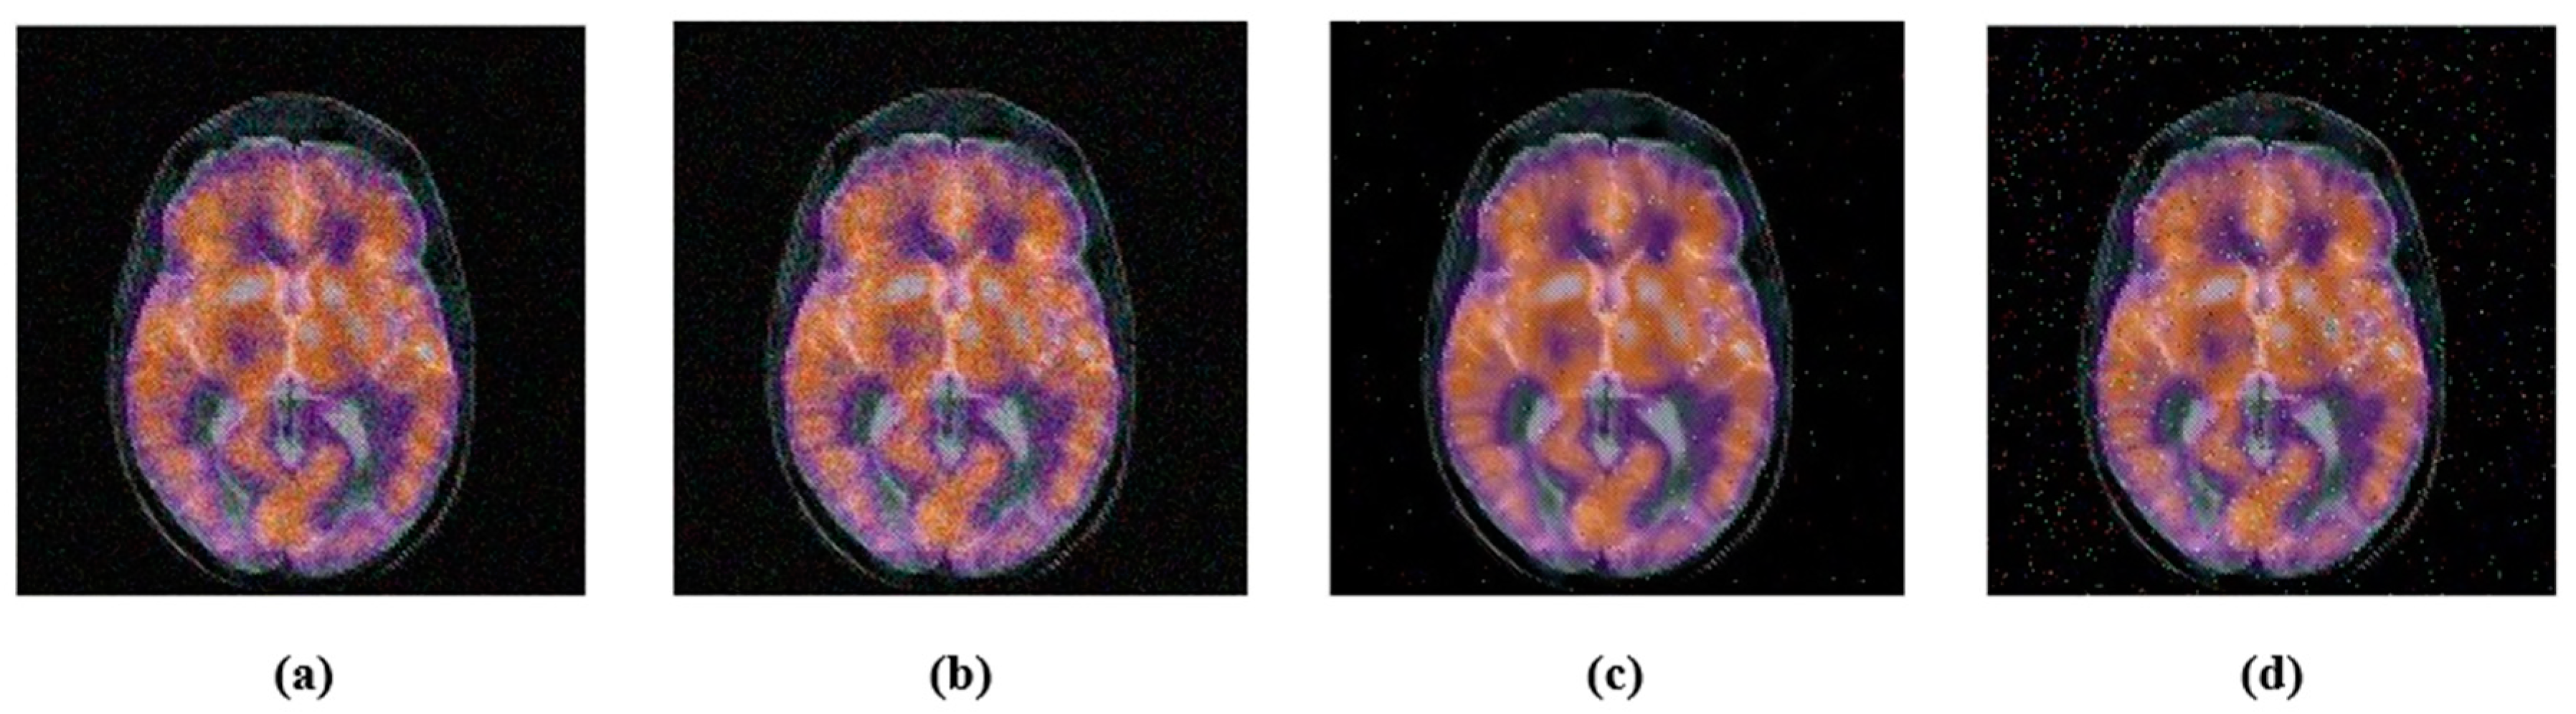

4.2. Robustness

4.2.1. Common Signal Processing Attacks

4.2.2. Geometric Attacks